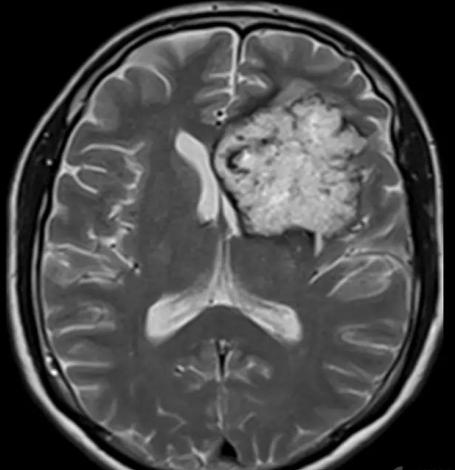

病例12

男,21岁,进行性右侧肢体无力1月。无发热、腹泻等病史。

答案:生殖细胞瘤。颅内生殖细胞瘤多发于儿童和青少年,以10~25岁多见。主要发生于颅内中线位置上,常见于松果体区和鞍区,发生在基底节区和丘脑的约占4%~10%,而松果体区是生殖细胞瘤最好发区。CT平扫为圆形不规则形或蝴蝶形、均匀等或稍高密度、有或无钙化和小囊变;强化可显现较小的囊变,多表现为中度到明显均匀一致的强化,少数不均匀强化。病灶周边有圆点状钙化。松果体区及鞍区同时发现肿瘤病灶则有利于生殖细胞瘤的诊断。MRI扫描多为等或稍长T1、稍长T2信号,偶尔T1混有高信号出血灶。均一强化、边界清楚,仅少数呈中等或不均匀强化。基底节区生殖细胞瘤肿瘤体积较大,但占位效应不明显、瘤旁水肿较轻。增强扫描时表现为不规则花环样强化或斑点样强化。